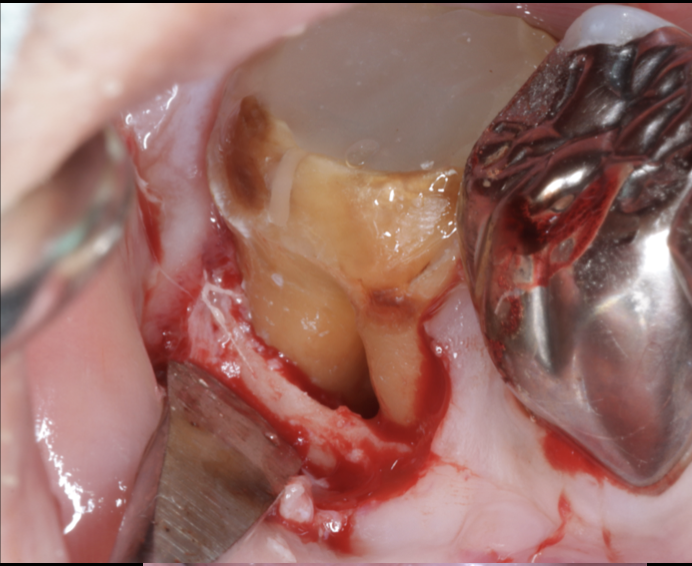

◆ 症例紹介(抜歯宣告から保存成功へ)

患者:50代男性

・前医で「歯根破折の疑い。抜歯が必要」と言われ来院

・マイクロスコープ下での観察により破折線なし

・根管治療+歯周再生療法+セラミック修復で保存成功

・現在も5年以上経過観察中で問題なし